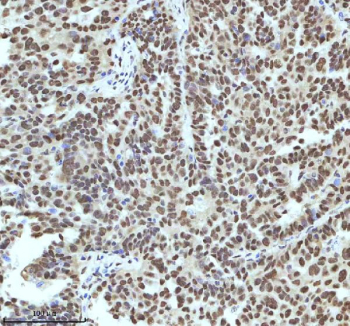

Immunohistochemical staining of IRF2BP1 using anti-IRF2BP1 antibody. IRF2BP1 was detected in a paraffin-embedded section of human cervical cancer tissue. Heat mediated antigen retrieval was performed in EDTA buffer (pH 8.0, epitope retrieval solution). The tissue section was blocked with 10% goat serum. The tissue section was then incubated with 2 ug/ml rabbit anti-IRF2BP1 antibody overnight at 4oC. Peroxidase Conjugated Goat Anti-rabbit IgG was used as secondary antibody and incubated for 30 minutes at 37oC. The tissue section was developed using an HRP secondary and DAB substrate.